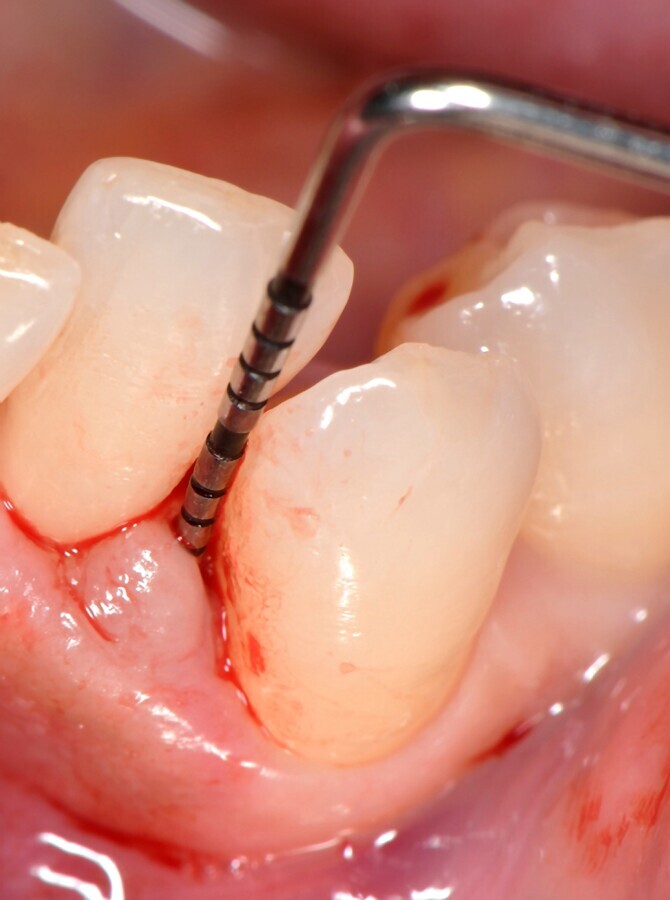

Figura 4. Sondaje periodontal. PPD de 6 mm y CAL de 7 mm para el diente 33.